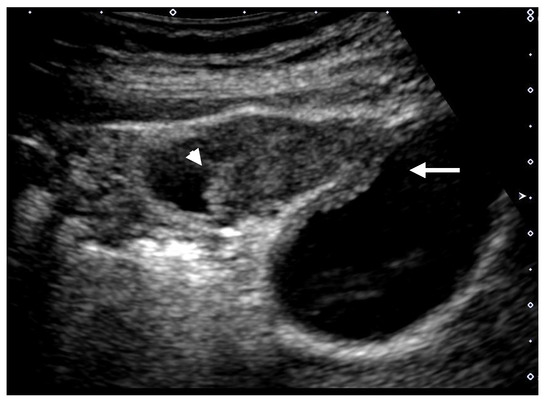

Figure 4. Focal presence of an inner hypoechoic layer (focal GWT). A high-frequency transducer with magnified image showed a slightly thickened inner hypoechoic layer less than 4-mm thick (arrow) in the fundus of GB (GBC case).

GWTs should be determined as wall thickening of 4 mm or more, and subdivided into diffuse and focal [1]. The presence of a partial inner hypoechoic layer of less than 4 mm in thickness (Figure 4) should also be included in focal GWT [1], as it may correspond to early-stage wall-thickening GBC. Diffuse GWT is not a specific US finding for GB abnormalities such as cholecystitis and GBCs; it can also occur in systemic diseases or inflammation of organs adjacent to the GB. However, focal GWT is a specific finding for the GB and is associated with a high frequency of malignant lesions. As GWTs, especially focal lesions, are more difficult to pick up than GPLs, magnification with a high-frequency transducer is strongly recommended (Figure 2). In addition, US evaluation should be performed after appropriate fasting time to rule out the effect of the postprandial contraction.